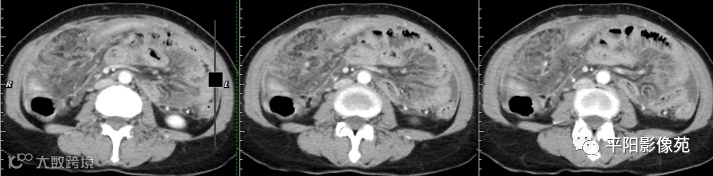

壁腹膜增厚伴或不伴腹水;增厚的腹膜光滑、均匀,呈线带状,部分可见腹膜结节,网膜及肠系膜广泛浸润性改变;增强扫描明显强化。

合并淋巴结肿大,可钙化,若中心干酪样坏死,增强扫描环形强化

湿型:渗出性高密度腹水(CT值20-45HU),高密度由于高蛋白和细胞含量多可能。

干型:干酪性肠系膜淋巴结病、纤维粘连、增厚,网膜饼状改变